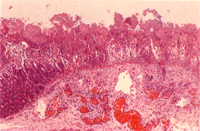

三 、 組織病變: 1. 空、迥腸 :空迴腸呈瀰漫性淺層凝固樣壞死,粘膜層被壞死膜取代,局部壞死區深入粘膜下層,形成明顯的炎症帶,壞死區可見大量細菌團塊,粘膜下層有明顯氣腫(圖4)。